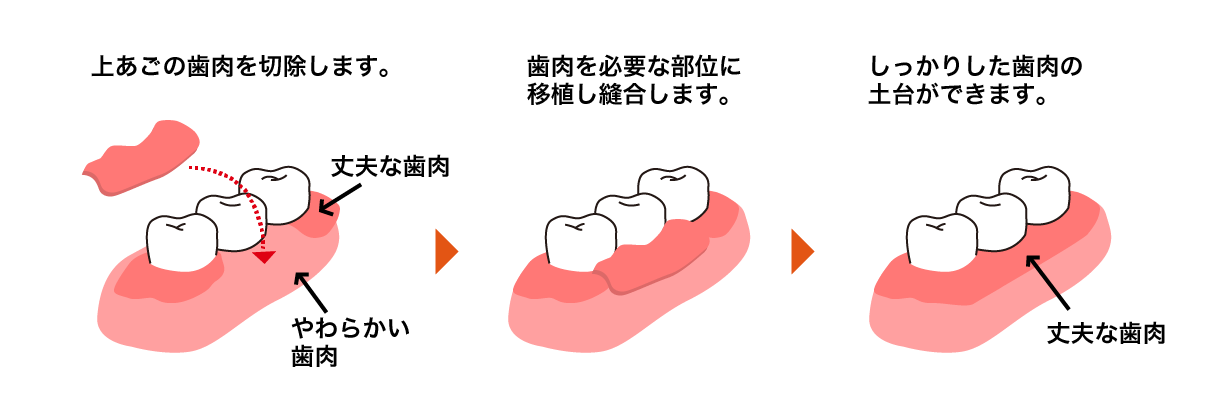

歯肉-歯槽粘膜手術

■弱い歯茎を強くて頑丈な歯茎にする

■歯茎が痩せてしまうのを防ぐ

■根の露出を防ぎ、虫歯を予防する

■歯ブラシのしやすい歯茎にする上顎の裏側の頑丈な歯茎を弱くなってしまった歯茎に移植する